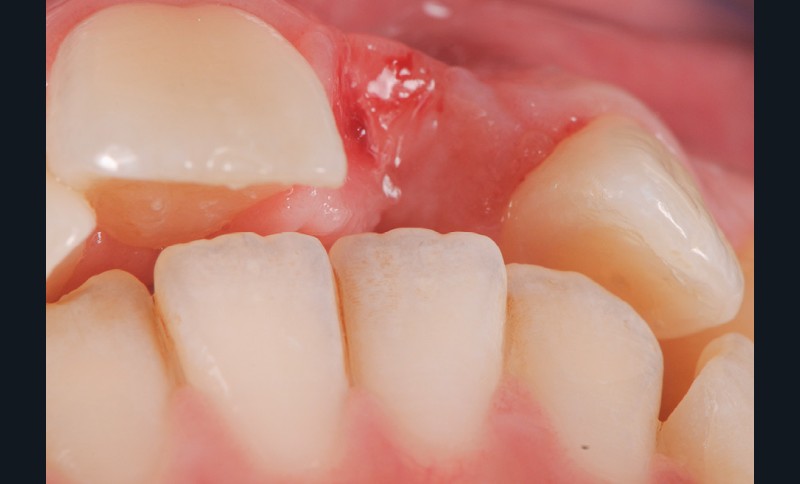

- Il faut aussi anticiper la nécessité d’une greffe de conjonctif au niveau du futur nouveau pontique compte tenu de la perte de tissus (effondrement en vestibulaire de la crête)

- De même, il faut anticiper le mode de temporisation en se servant de cet ancien bridge collé en temporisation (assemblé au CVIMAR avec un peu de glycérine pour en faciliter la dépose) pendant la phase de cicatrisation parodontale (12 semaines post-opératoires environ), puis la réalisation d’une gouttière avec une centrale du commerce en résine à l’issue du temps de maturation parodontale pour la préparation…